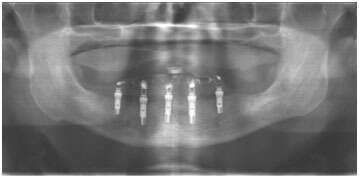

NobelGuide est un système à la fois puissant et polyvalent, dont l'utilisation est aussi facile qu'intuitive. Avec NobelGuide, toutes les décisions importantes peuvent être considérées avant toute intervention chirurgicale.